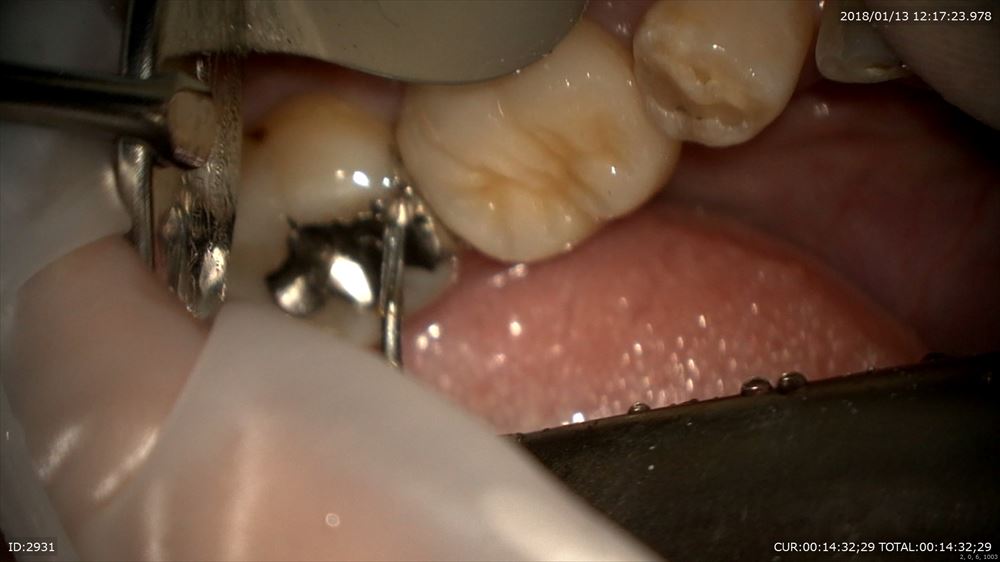

精密根管治療の難しい所は根管内だけではありません。この方は右上7番一番アプローチしずらい所。

難しいのはいかに上部形成を行うか。エンドの基本。その為の準備

まず被せ物を外し

ここからコアを除去。金属が口に入ったり口を絶対に傷つけないためのラバーダム(必須!!)金属を飲んだら大変です。ラバーダムをしないで根管治療を行う事は当院では100%ありません。